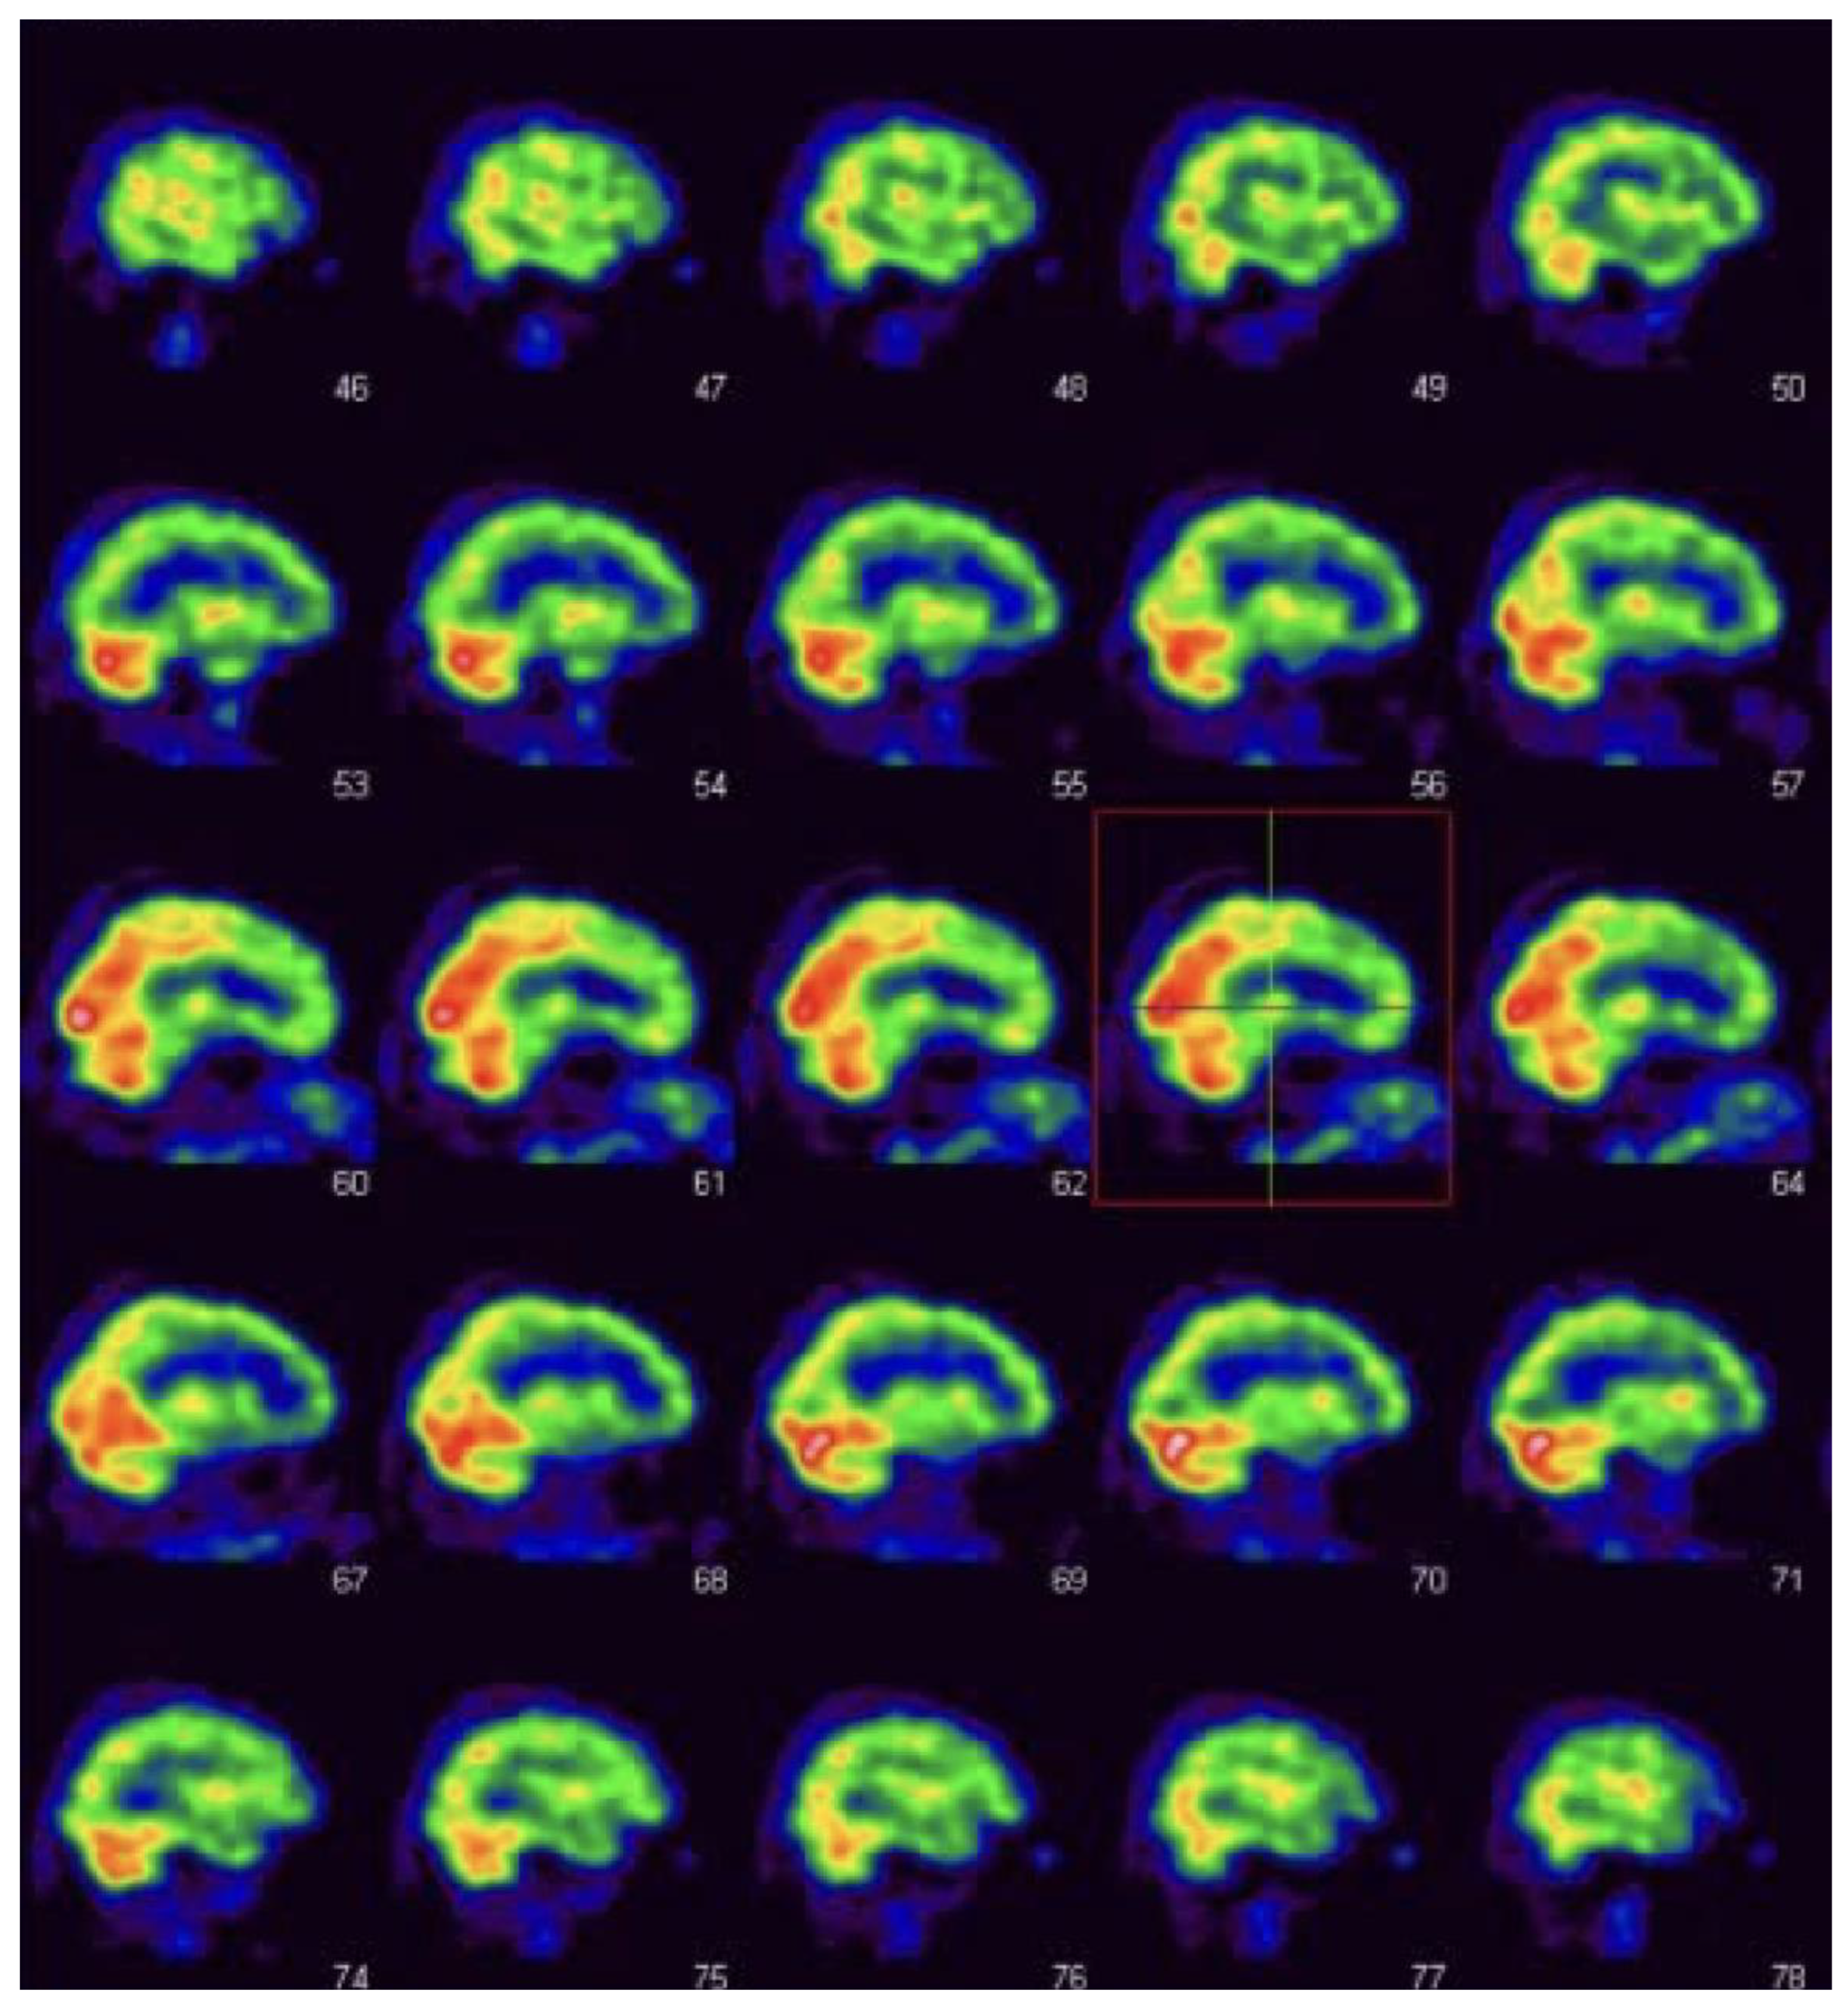

2.2. SPECT